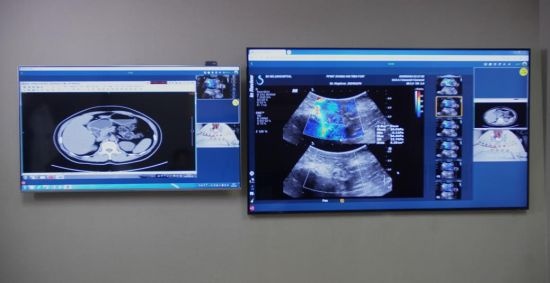

近日,三星QLED 8K電視正式入駐該實驗室,用于醫療場景的創新應用,為廣大醫療工作者的日常工作帶來更有力的保障。

三星QLED 8K電視正式入駐上海十院5G超聲聯合創新實驗室

除了5G的“速度”外,終端顯示也很重要。“超

高清”顯示設備在其中起著不可或缺的作用。“越清楚越好”,郭樂杭強調,超聲等影像

技術對于圖像質量的追求是永無止境的,比起以往的4K顯示器,QLED 8K電視讓畫面更加清晰、明亮,也讓醫生們能夠為廣大患者做出“一個更好的診斷”。